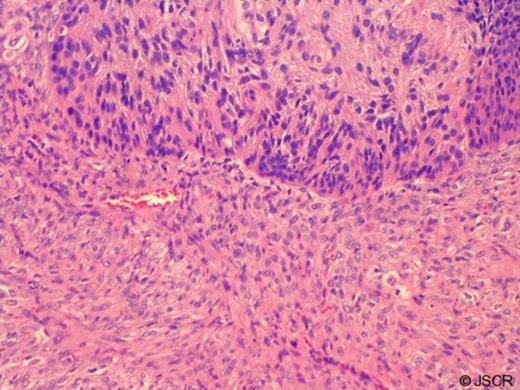

Surgical pathology report of the specimen from the operating room demonstrated in situ and invasive squamous cell carcinoma, which was previously identified in the endoscopic specimen, but there were also sarcomatous areas. This is depicted inFigure 2. The tumor measured 6 cm, was exophytic and high grade, and invaded into the submucosa but not the muscularis propria. The surgical margins and a resected celiac lymph node were negative, and there was no lymphovascular invasion. Based on the findings of both squamous cell and sarcomatous cell types, the final diagnosis was oesophageal carcinosarcoma, and it was classified as stage T1 N0 M0.

Surgical pathology: squamous cell and sarcomatous cell components of oesophageal carcinosarcoma, hematoxylin and eosin stain at 100x magnification